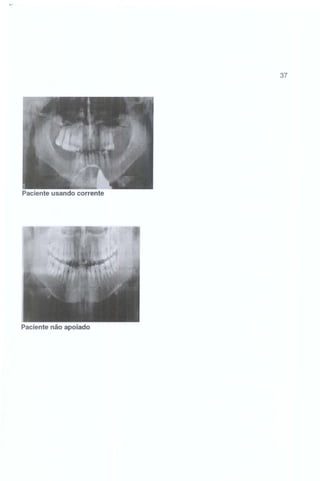

Paciente usando corrente

Paciente não apoiado